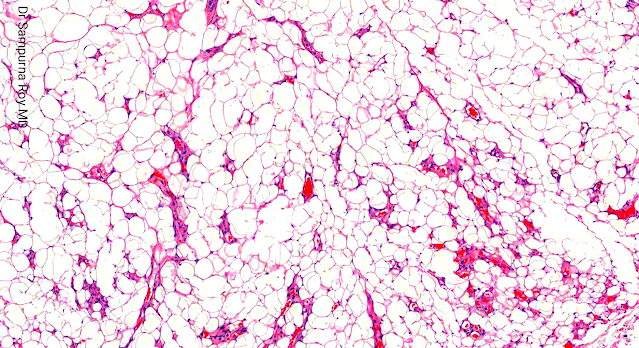

Dermatopathology Case 193 Get link Facebook X Pinterest Email Other Apps April 08, 2022 A 28 year old male with a subcutaneous lesion on the left forearm. Answer Get link Facebook X Pinterest Email Other Apps Comments